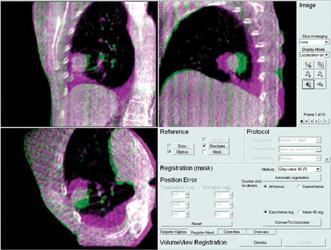

Siemens and Philips demonstrated examples of new imaging software to convert MRI datasets into synthetic computed ...